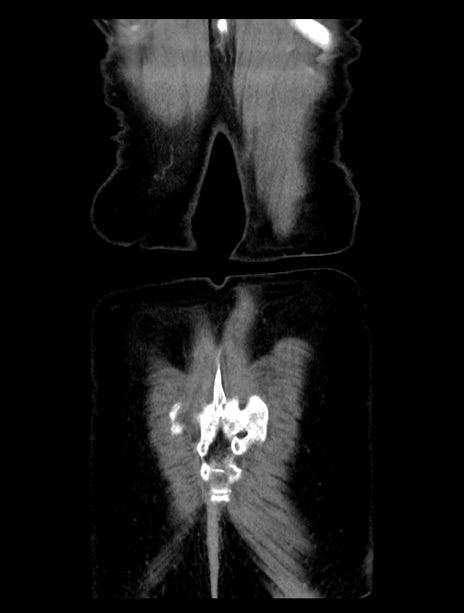

症例23(冠状断像)

【症例】70歳代女性

【主訴】下腹部痛・嘔吐

【現病歴】2日前より腹痛あり。昨日嘔吐あり。症状改善しないため来院。

【既往歴】胃GISTに対して胃部分切除後。

【身体所見】BT 37.1℃、BP 128/77mmHg、腹部:平坦・軟、下腹部に圧痛あり。

【データ】WBC 10200、CRP 0.31